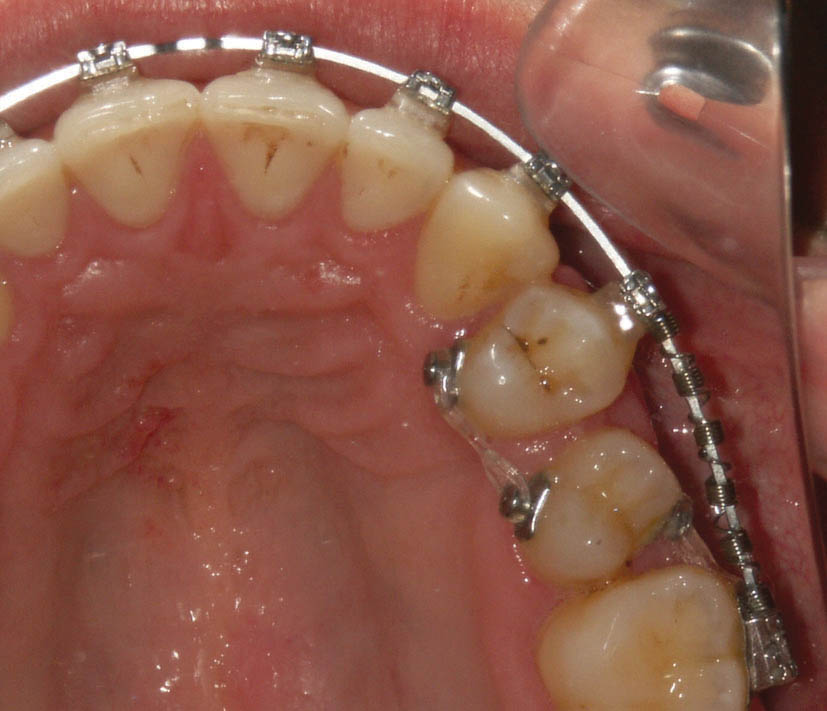

همانطور که دیدید یکی از عوارض چین الاستیک ایجاد چرخش در دندانها است. در شکل 162-1 میبینید که باکال پرمولر دوم به سمت مزیال چرخش دارد، لذا قطعهای از چین الاستیک را از باکال این دندان به مولر اول و از پالاتال به پرمولر اول انداختهایم تا با ایجاد چرخش در پرمولر باعث اصلاح موقعیت آن گردد (شکل 163-1).

شکل 162-1: ایجاد چرخش در دندان به کمک Chain Elastic

شکل 163-1: دو ماه بعد تا حدود زیادی چرخش پرمولر دوم درست شده است.